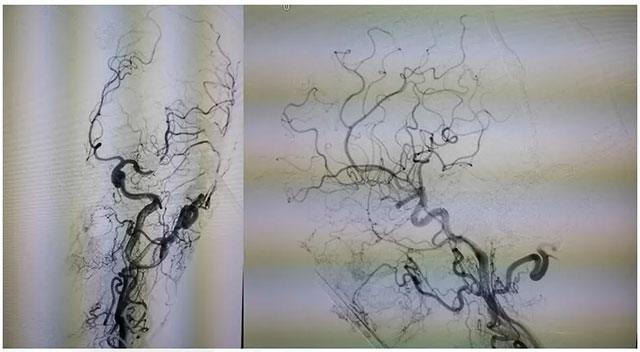

▲ DSA检查显示,左侧窦区动静脉瘘

DSA 检查显示,左侧窦区动静脉瘘,静脉瘘术后改变,供血动脉为枕动脉,通过皮层静脉引流至横窦,左侧椎动脉通过肌支供血汇入枕动脉。